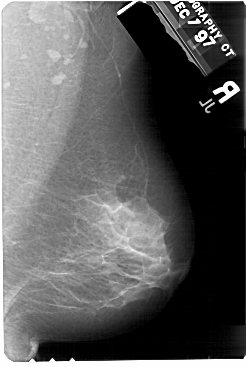

A_1584_1.LEFT_MLO

LEFT_MLO LINES 5491 PIXELS_PER_LINE 3421 BITS_PER_PIXEL 12 RESOLUTION 43.5 OVERLAY